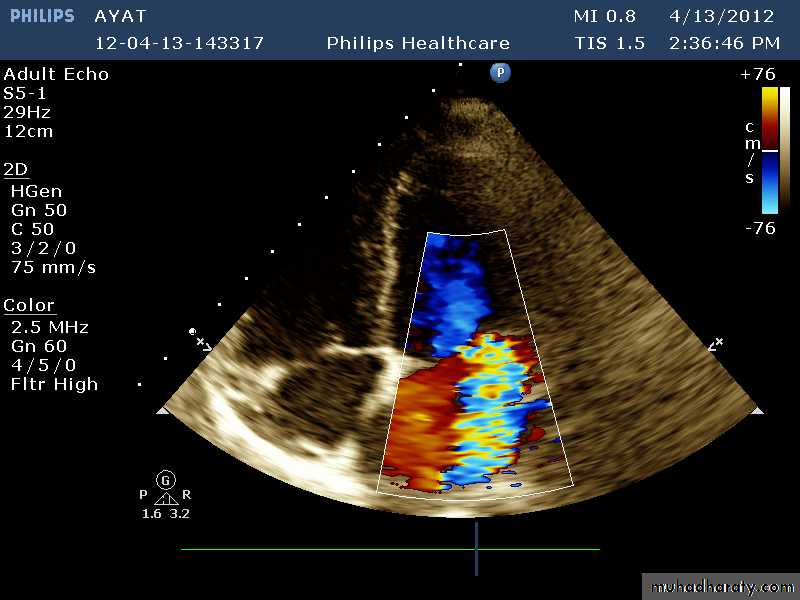

VEGETATIONS

36

37

38

39

40